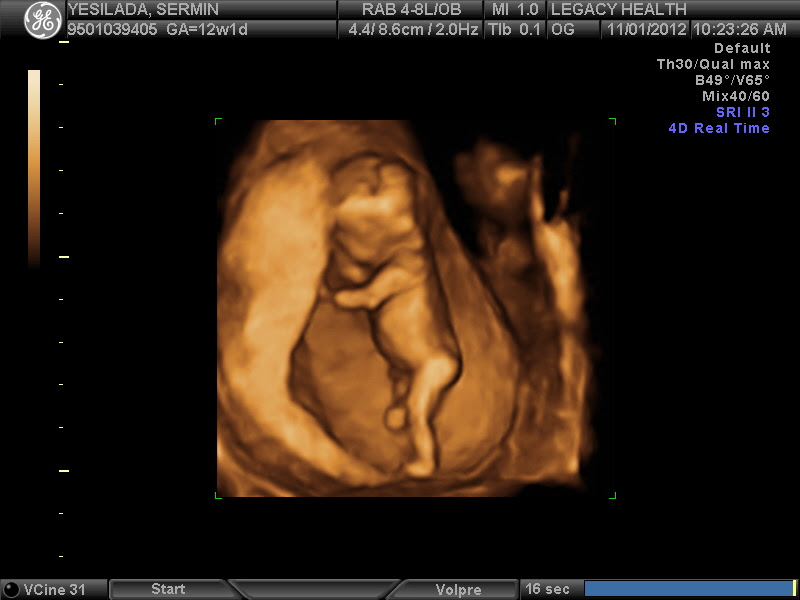

Проводя ультразвуковое исследование, врач оценивает состояние матки, место крепления плаценты, устанавливает приблизительный срок ваших родов.

На УЗИ вы увидите, как малыш двигается, сгибая и разгибая ножки и ручки. Можно попросить доктора сделать на сроке беременность 13 недель фото УЗИ.

13 неделя беременности: фото ребенка уже похоже на снимок маленького человечка. В 13 недель беременности фото плода дает представление не только о его размерах, но и показывает его ножки и ручки с маленькими пальчиками.

Сейчас, на ранних сроках беременности, УЗИ помогает выявлять возможные пороки развития и врожденные аномалии плода. Помните — результаты УЗИ никогда не трактуются, как окончательный диагноз. Они являются поводом для дальнейшего, более глубокого и всестороннего обследования будущей мамы с последующими консультациями у профильных специалистов.